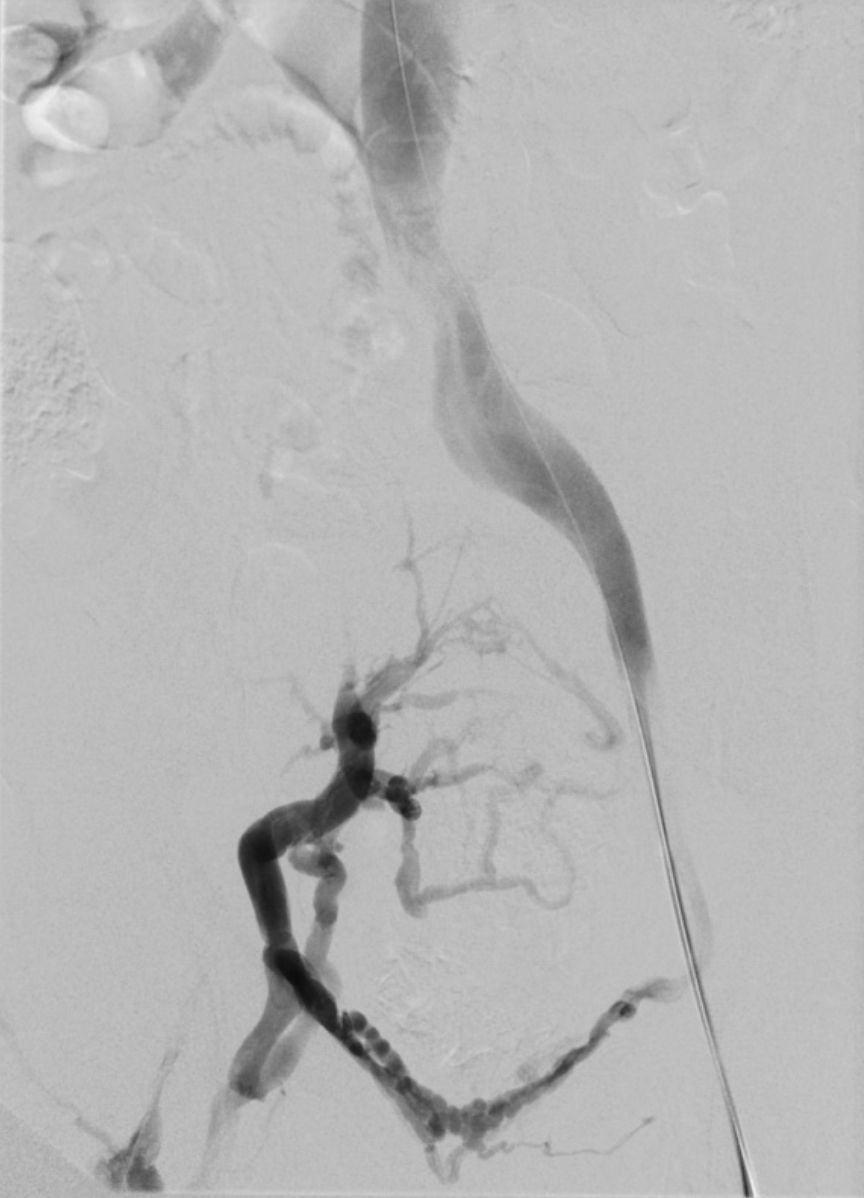

Beispiel eines Patienten mit Postthrombotischem Syndrom des rechten Beines (Schmerzen und Schwellung). Verschluss der Beckenvenen rechts.

Rekanalisation mit Dilatation und Stents der rechtsseitigen Beckenvenen. Hierdurch wieder freier Fluss in den Beckenvenen.